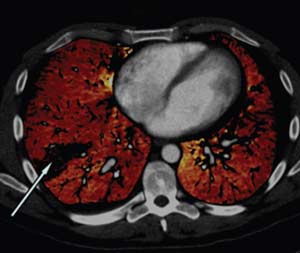

• Image of dual energy CT visualizing blood perfusion deficits

Perfusion Blood Volume Imaging

Dual energy CT can be utilized to visualize blood perfusion deficits (arrow) secondary to the presence of pulmonary emboli. The colored regions indicate the perfused blood volume.